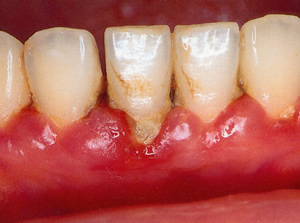

歯肉炎

これが最初の兆候です。プラーク、歯石の沈着で歯肉に赤み、腫れ、出血がみられます。

簡単な歯石取りやブラッシングで改善することが出来ます。 |